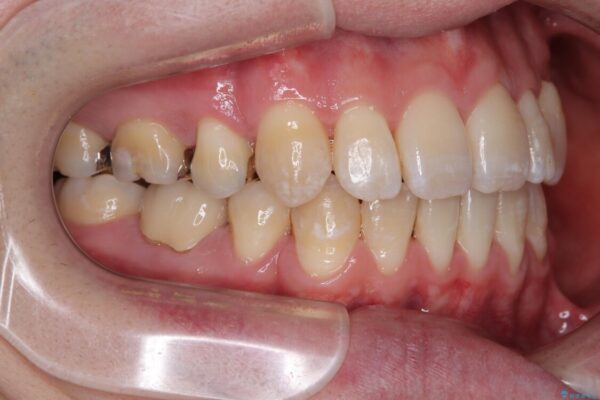

治療前

• 口元の突出感を改善!目立ちにくいワイヤー矯正で自信を持てる自然な横顔に 治療前画像

精密検査の結果、上下左右の小臼歯4本を抜歯し、そのスペースに前歯を後方へ移動させる矯正治療をご提案しました。

装置は、透明感のあるクリアブラケットとホワイトコーティングされたワイヤーを使用した、目立ちにくい審美装置を選択。